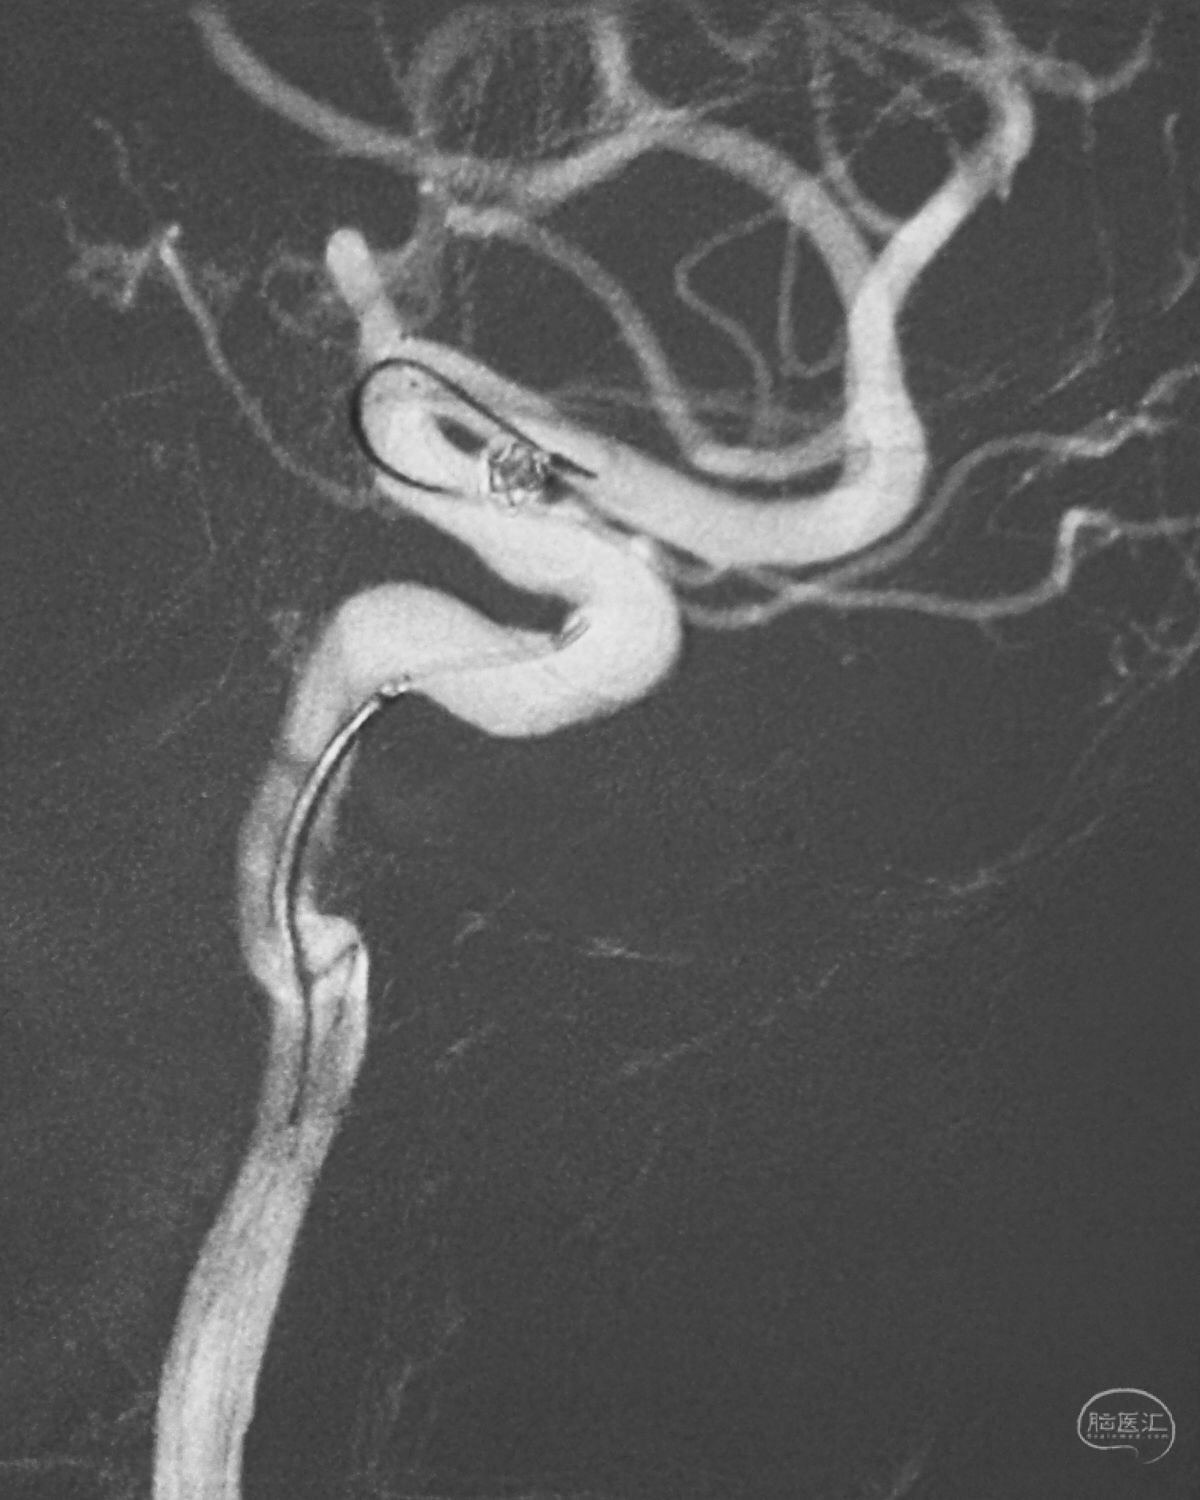

Echelon 10微导管头无论塑成C形还是S形,均无法稳定于动脉瘤腔内,遂使用回马枪技术,使微导管成襻通过,管头折返入瘤腔。

跨瘤颈释放Solitaire 4×20支架(蓝线),压住微导管(红线),在支架保护下经返折的微导管送入弹簧圈填塞瘤腔。

依次送入QC-2-4-3D,2-3-Helix,1.5-2-Helix,1.5-2-Helix四枚弹簧圈,最后一枚弹簧圈将管头(箭头)顶出瘤腔。